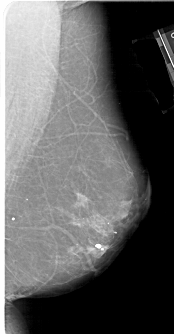

A_1647_1.LEFT_MLO

LEFT_MLO LINES 6781 PIXELS_PER_LINE 3631 BITS_PER_PIXEL 12 RESOLUTION 43.5 OVERLAY